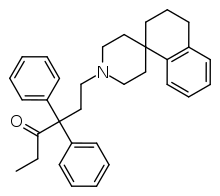

4-Phenylpiperidines

Others

Structures

| Other phenylpiperidines | |||

|---|---|---|---|

Alvimopan Alvimopan |

Loperamide Loperamide |

LS-115509 LS-115509 |

Picenadol Picenadol |